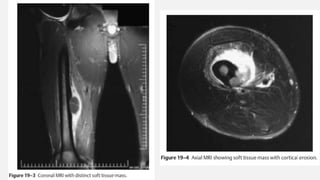

EWING’S SARCOMA FEMUR

• An otherwise healthy 20-year-old male developed a sudden increasing pain in his right

femur. The pain is so severe that he is unable to walk, needs crutches, and requires

high doses of narcotics. The pain awakes him from sleep. There is no history of

associated trauma. He has not noticed any pal- pable mass nor antecedent pain in his

right femur. Of note, he had a prior anterior cruciate ligament reconstruction on his

right side, but this procedure was done in the distant past and is unrelated to any of

his pain. He has actually had excellent rehabilitation from that procedure and tolerated

the procedure well. He has had no associated fever or chills. White count and

infectious laboratory work reveal normal sedimentation rate and C-reactive protein

(CRP). Anteropos- terior and lateral femur (Fig. 19–1 and Fig. 19–2) films show a lytic

lesion of the middiaphyseal region with a sun burst periosteal reaction. Magnetic

resonance imaging (MRI) (Fig. 19–3 and Fig. 19–4) revealed a soft tissue mass with a

right peritumoral inflammatory zone associated with it. The mass measures

approximately 5 × 4 × 3 cm. Computed tomogra- phy (CT) scan shows cortical

erosions as well. A chest CT also was performed, showing no obvious pulmonary

metastases. A bone scan was ordered as well (Fig. 19–5).

EWING’S SARCOMA FEMUR •An otherwise healthy 20-year-old male developed a sudden increasing pain in his right femur. The pain is so severe that he is unable to walk, needs crutches, and requires high doses of narcotics. The pain awakes him from sleep. There is no history of associated trauma. He has not noticed any pal- pable mass nor antecedent pain in his right femur. Of note, he had a prior anterior cruciate ligament reconstruction on his right side, but this procedure was done in the distant past and is unrelated to any of his pain. He has actually had excellent rehabilitation from that procedure and tolerated the procedure well. He has had no associated fever or chills. White count and infectious laboratory work reveal normal sedimentation rate and C-reactive protein (CRP). Anteropos- terior and lateral femur (Fig. 19–1 and Fig. 19–2) films show a lytic lesion of the middiaphyseal region with a sun burst periosteal reaction. Magnetic resonance imaging (MRI) (Fig. 19–3 and Fig. 19–4) revealed a soft tissue mass with a right peritumoral inflammatory zone associated with it. The mass measures approximately 5 × 4 × 3 cm. Computed tomogra- phy (CT) scan shows cortical erosions as well. A chest CT also was performed, showing no obvious pulmonary metastases. A bone scan was ordered as well (Fig. 19–5). Orthopedic Oncology by Ernest Conrad Thieme